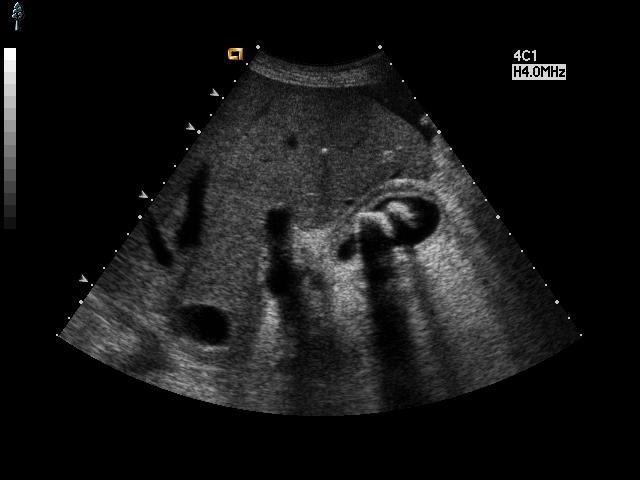

超然精彩病例欣赏之——急性胆囊炎并胆囊结石,胆泥团形成 - 超声医学

急性胆囊炎超声——胆囊壁增厚( 4.2mm ),胆囊周围渗出